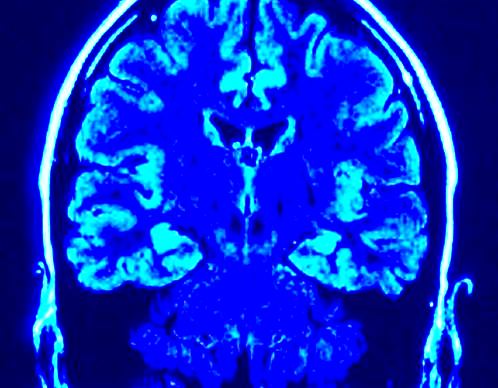

Identyfikacja choroby Azheimera

Hiszpańscy badacze zidentyfikowali właśnie marker, który jest obecny w płynie mózgowo-rdzeniowym i który pozwoli na łatwiejsze i szybsze diagnozowanie i leczenie choroby Alzheimera. I to aż 10 lat przed pojawieniem się objawów tych problemów neurodegeneracyjnych.

Hiszpańscy naukowcy udowodnili, że niskie poziomy DNA mitochondrialnego w płynie mózgowo-rdzeniowym są nie tylko przedklicznicznym wskaźnikiem choroby Alzheimera, ale także jedną z jej przyczyn!

Kolejna dobra wiadomość: test pozwalający wykrywać niskie poziomy DNA mitochondrialnego w płynie mózgowo-rdzeniowym jest jak najbardziej wykonalny dzięki prostej technice, zwaną metodą PCR (ang. Polymerase Chain Reaction).

Jeżeli więc badania pójdą jeszcze dalej, być może już za kilka lat naukowcy będą mieli możliwość potwierdzania poziomu DNA mitochondrialnego w płynie mózgowo-rdzeniowym metodą prostego testu. Tym samym prewencja choroby będzie wykonalna, i to jeszcze przed pojawieniem się pierwszych objawów.